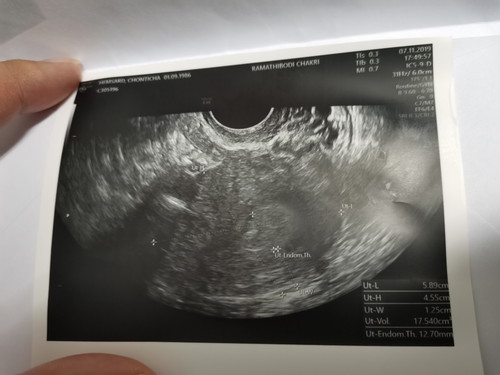

เมื่อวานไปตรวจกับหมอ หมอซาวด์ยังไม่เจออะไรเลย ว่างเปล่า หมอบอกว่าน่ากลัวจะท้องนอกมดลูก ค่าเลือดBeta Hcg อยู่ที่400กว่าๆ หมอนัดอีกอาทิตย์นึง ไปตรวจเลือดใหม่ ถ้าค่าเลือดยังไม่เพิ่มสูงหรือลดลง ก็คงมีสิทธิ์แท้ง กังวลมากเลยตอนนี้ (5สัปดาห์แล้วค่ะ)